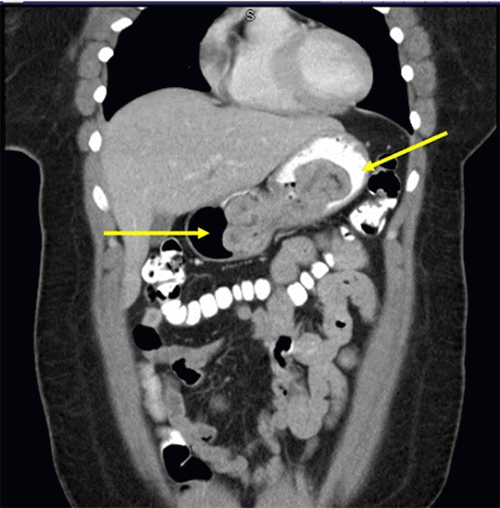

Our patient was an obese, 41-year-old woman who presented with a three-year history of reflux and early satiety without significant weight loss. She tolerated her diet without nausea or vomiting and reported normal bowel function. She received an upper endoscopy that revealed a small hiatal hernia and large, noncircumferential, frond-like, villous masses with extensive intragastric extension. A CT scan of the abdomen demonstrated the extent of the masses as well (see Figure 1). The biopsies of the masses were evaluated by two different pathologists; they both determined that the lesions were gastric xanthoma. She then underwent an endoscopic ultrasound, where deeper biopsies of the lesions were taken and were concordant with the diagnosis of xanthoma without pathologic evidence of carcinoma. She was then referred to surgical oncology for definitive care.

Figure 1. Preoperative CT Scan Demonstrates Gastric Xanthoma (arrows). Published with Permission

Image confirmed a large, well-defined mass within the gastric body